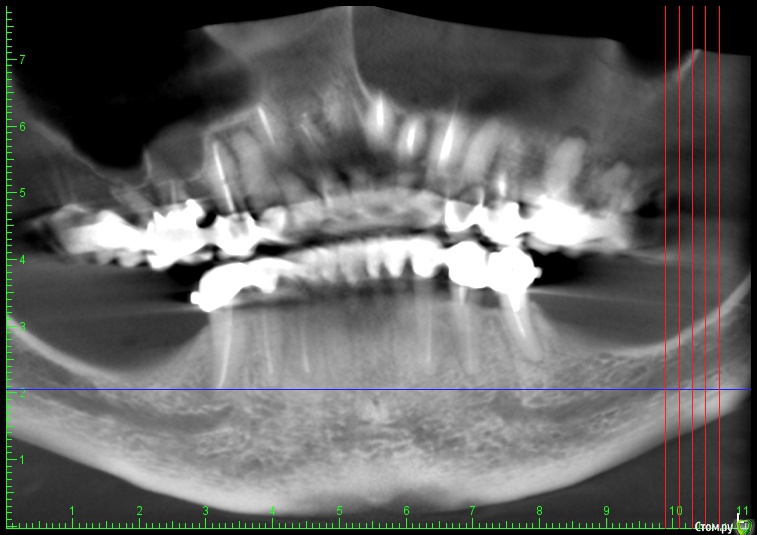

Глеб Митрофанов Опубликовано 22 октября, 2015 Автор Поделиться Опубликовано 22 октября, 2015 Срезы кт Ссылка на комментарий

basha.ru Опубликовано 23 октября, 2015 Поделиться Опубликовано 23 октября, 2015 Спасибо за кейс.Скажите пожалуйста какая высота кости до нижнечелюстного канала?Спасибо. Ссылка на комментарий

Глеб Митрофанов Опубликовано 23 октября, 2015 Автор Поделиться Опубликовано 23 октября, 2015 (изменено) Спасибо за кейс.Скажите пожалуйста какая высота кости до нижнечелюстного канала?Спасибо.До канала , в самой низшей точке - 4,5-5 мм Изменено 23 октября, 2015 пользователем Глеб Митрофанов Ссылка на комментарий